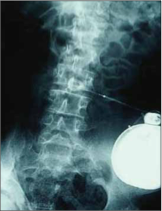

Поэтому чтобы достичь наилучшего эффекта с небольшими дозами, баклофеновую помпу фиксируют непосредственно в субарахноидальное пространство позвоночника что дает гораздо более эффективные результаты. ГАМК-зависимое ингибирование уменьшает спастичность, без побочных неврологических эффектов.

Мы можем перечислить необходимые показания для проведения этой операции установки баклофеновой помпы следующим образом:

Обязательно необходимо учитывать физическое состояние пациента. Чтобы избежать каких-либо проблем из-за объема насоса, пациент должен быть не менее 15 кг и старше 3 лет.

Цель установки интратекальной баклофеновой помпы; дать возможность пациенту сидеть в инвалидной коляске, чувствовать себя более комфортно, предотвратить деформации позвоночника, уменьшать спастичность и облегчить уход за пациентом.